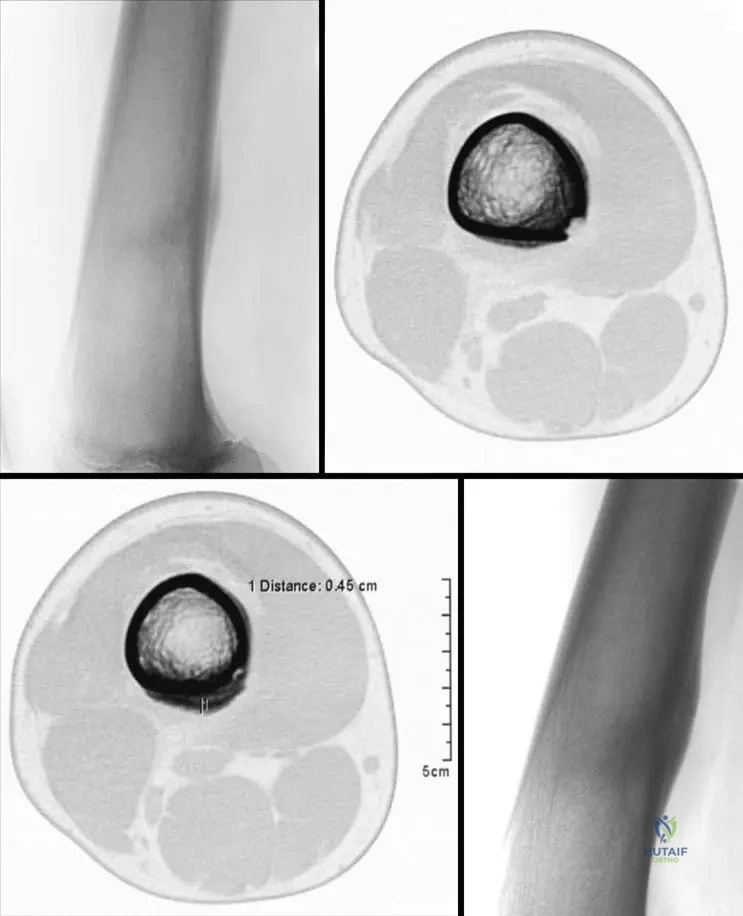

A 60-year-old man with a history of diabetes mellitus presents with a swollen, deformed, and insensate right ankle. He denies any significant trauma. Physical examination reveals a warm, erythematous, and unstable ankle joint with palpable crepitus. Radiographs show severe disorganization of the ankle joint, fragmentation of the talus, and extensive new bone formation.

View Answer & Explanation

Correct Answer: D

Rationale: The combination of a deformed, swollen, unstable, and insensate joint in a patient with diabetes, along with radiographic evidence of severe joint disorganization and new bone formation, is characteristic of Neurogenic Osteoarthropathy, also known as Charcot’s Joint. Diabetes is a common cause. Gout and bacterial arthritis are typically acute and painful. Osteoarthritis is a degenerative process, usually less destructive and not insensate. Reflex sympathetic dystrophy involves pain and autonomic dysfunction, not primary joint destruction.